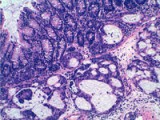

El proyecto del CIMA estudia el papel de una nueva terapia para diversas neoplasias hematológicas. “En concreto, hemos desarrollado y evaluado péptidos moduladores de la actividad de la proteína intercambiadora de iones SLC4A2, que ejercen un potente y doble efecto antitumoral”, explica José A. Martínez-Climent, director del trabajo.

El experto asegura que, por un lado, “inducen apoptosis de las células linfoides B neoplásicas y, por otro, potencian la respuesta inmune antitumoral mediante el bloqueo de la función de los linfocitos T reguladores”.

“A partir de ahora nuestra investigación se va a centrar en demostrar el potencial terapéutico de las moléculas inhibidoras de SLC4AE2 en modelos experimentales de linfoma, leucemia y mieloma, y en muestras obtenidas de pacientes con estas enfermedades. El objetivo final es avanzar hacia la aplicación clínica de esta nueva terapia”, explican Juan José Lasarte y Juan Francisco Medina, otros investigadores del proyecto, en el que también participan Felipe Prósper y María José Calasanz, de la Universidad de Navarra. (Fuente: CIMA de la Universidad de Navarra)